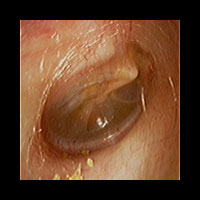

右急性中耳炎(重症) 鼓膜切開

鼓膜が赤く腫れて、鼓膜の奥に白い膿がたまっています。高熱が続き、痛みがとても強かっため、鼓膜切開を行いました。

9日目にほぼ治りました。当院ではできる限り鼓膜切開を行わずに治すことを考えていますが、必要な時はお勧めしています。

初診時 鼓膜切開の直前

初診時 鼓膜切開の直後

9日目